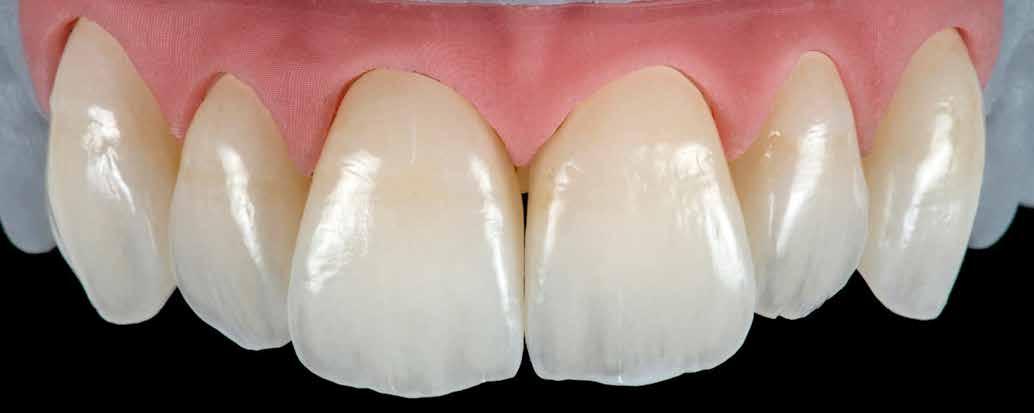

MED. DENT Abradált frontfogakkal rendelkező felnőtt páciens interdiszciplináris kezelése

2–4. képek: Festett példák.